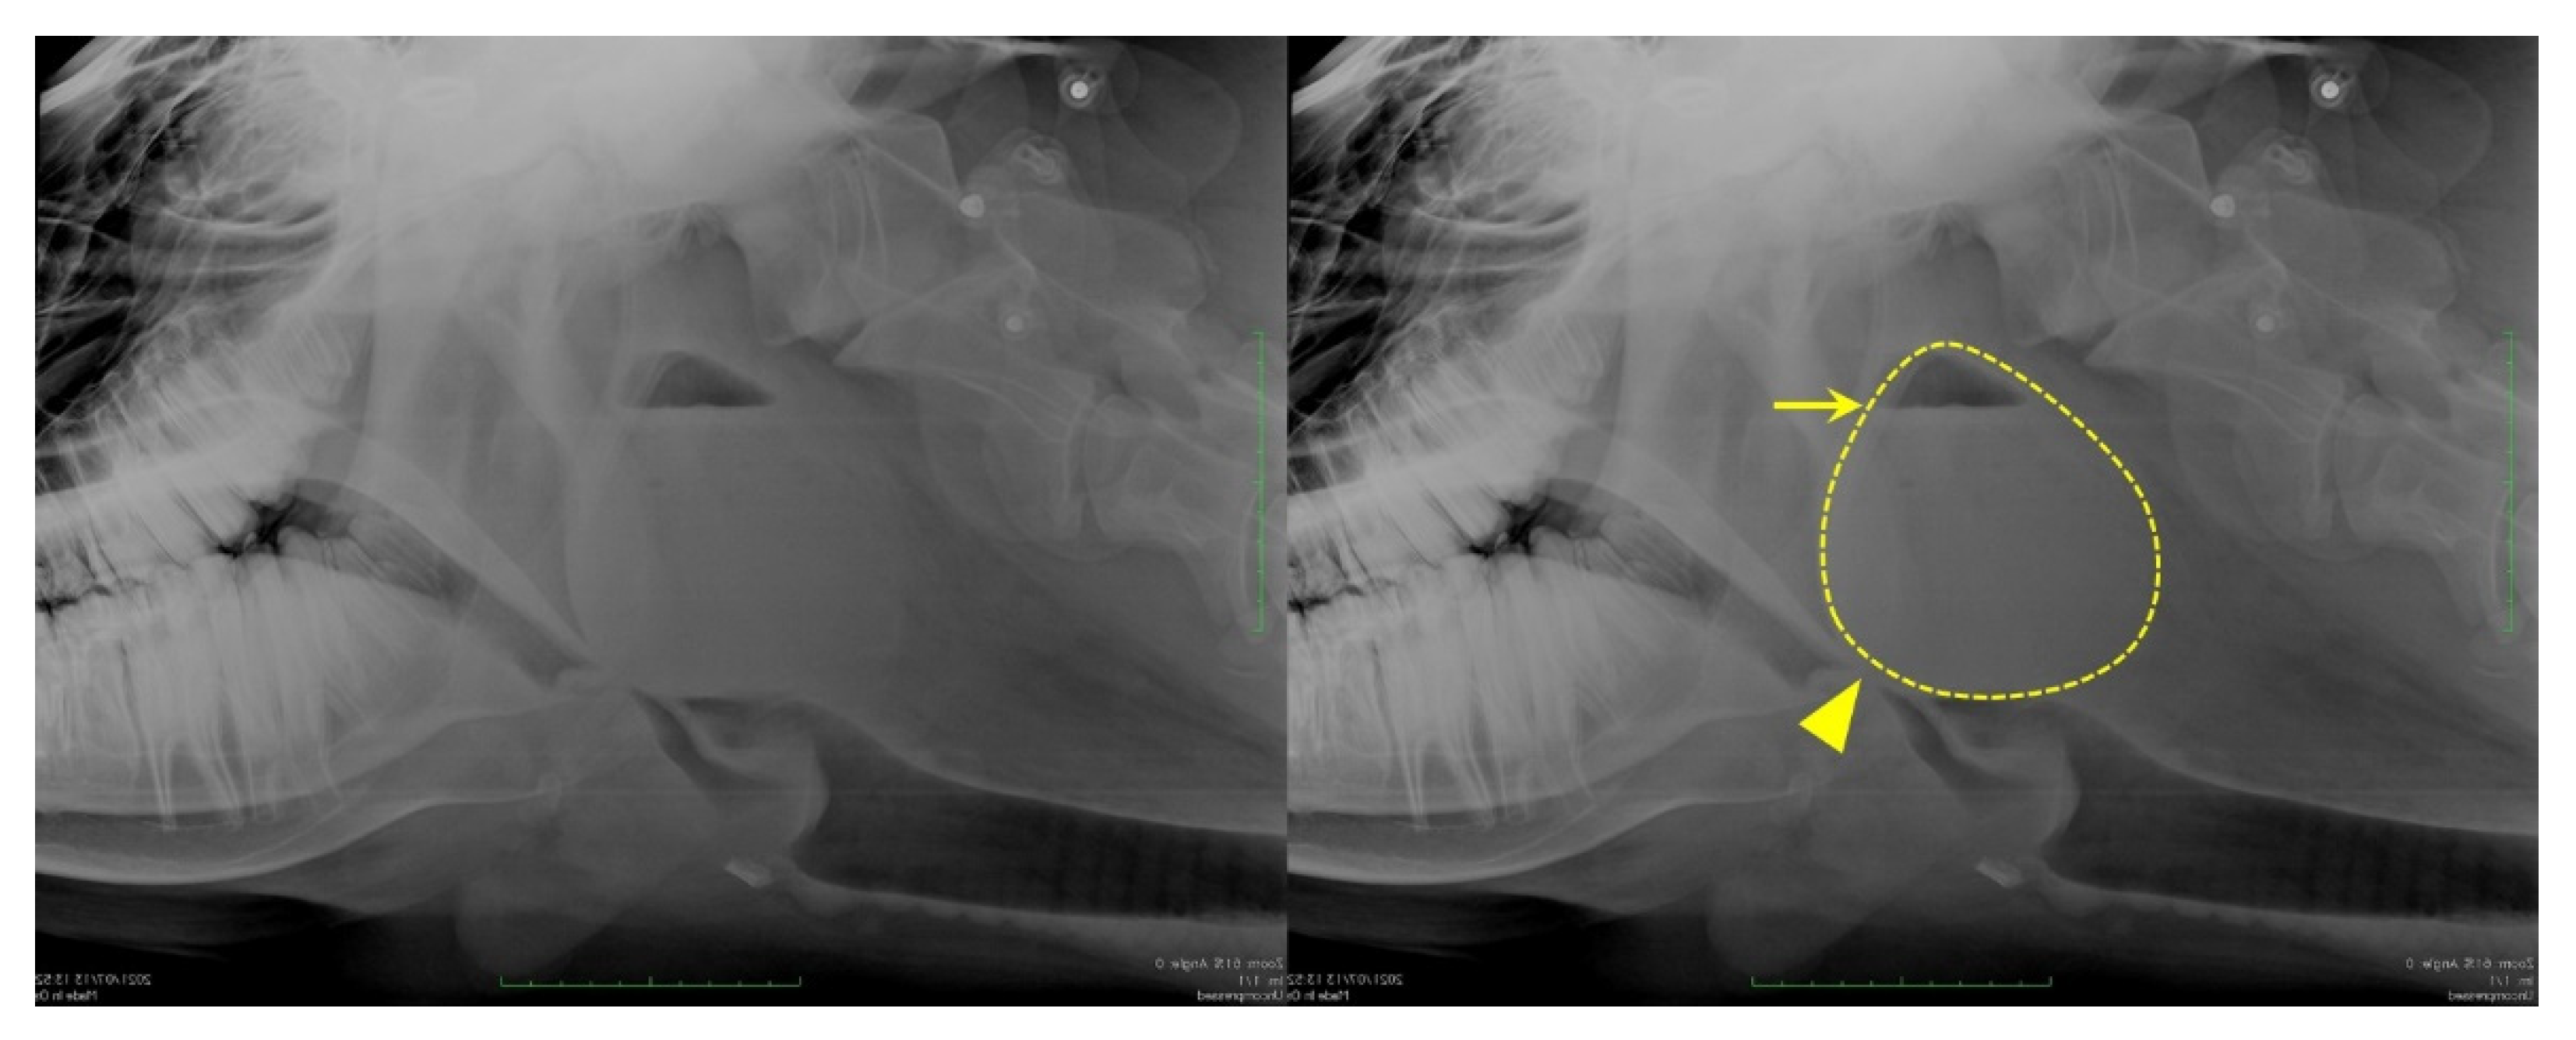

3.3. Ultrasonography

Ultrasonography (7.0–8.0 MHz variable linear probe, iViz air, FUJIFILM Healthcare, Tokyo, Japan) was performed without sedation, from the left side of the cow, using the trachea and epiglottic cartilage as landmarks. The interior of the mass was hypoechogenic, though not fluid (Figure 2).

Figure 2. Ultrasonography showing the retropharyngeal mass. The scan was performed from the left side of the cow, with the probe in a transverse position; the trachea and epiglottic cartilage present as landmarks. A mass can be identified on the dorsal surface of the arytenoid cartilage. Cr: cranial; Cd: caudal; Ac: arytenoid cartilage; Tr: trachea area; ※: mass.